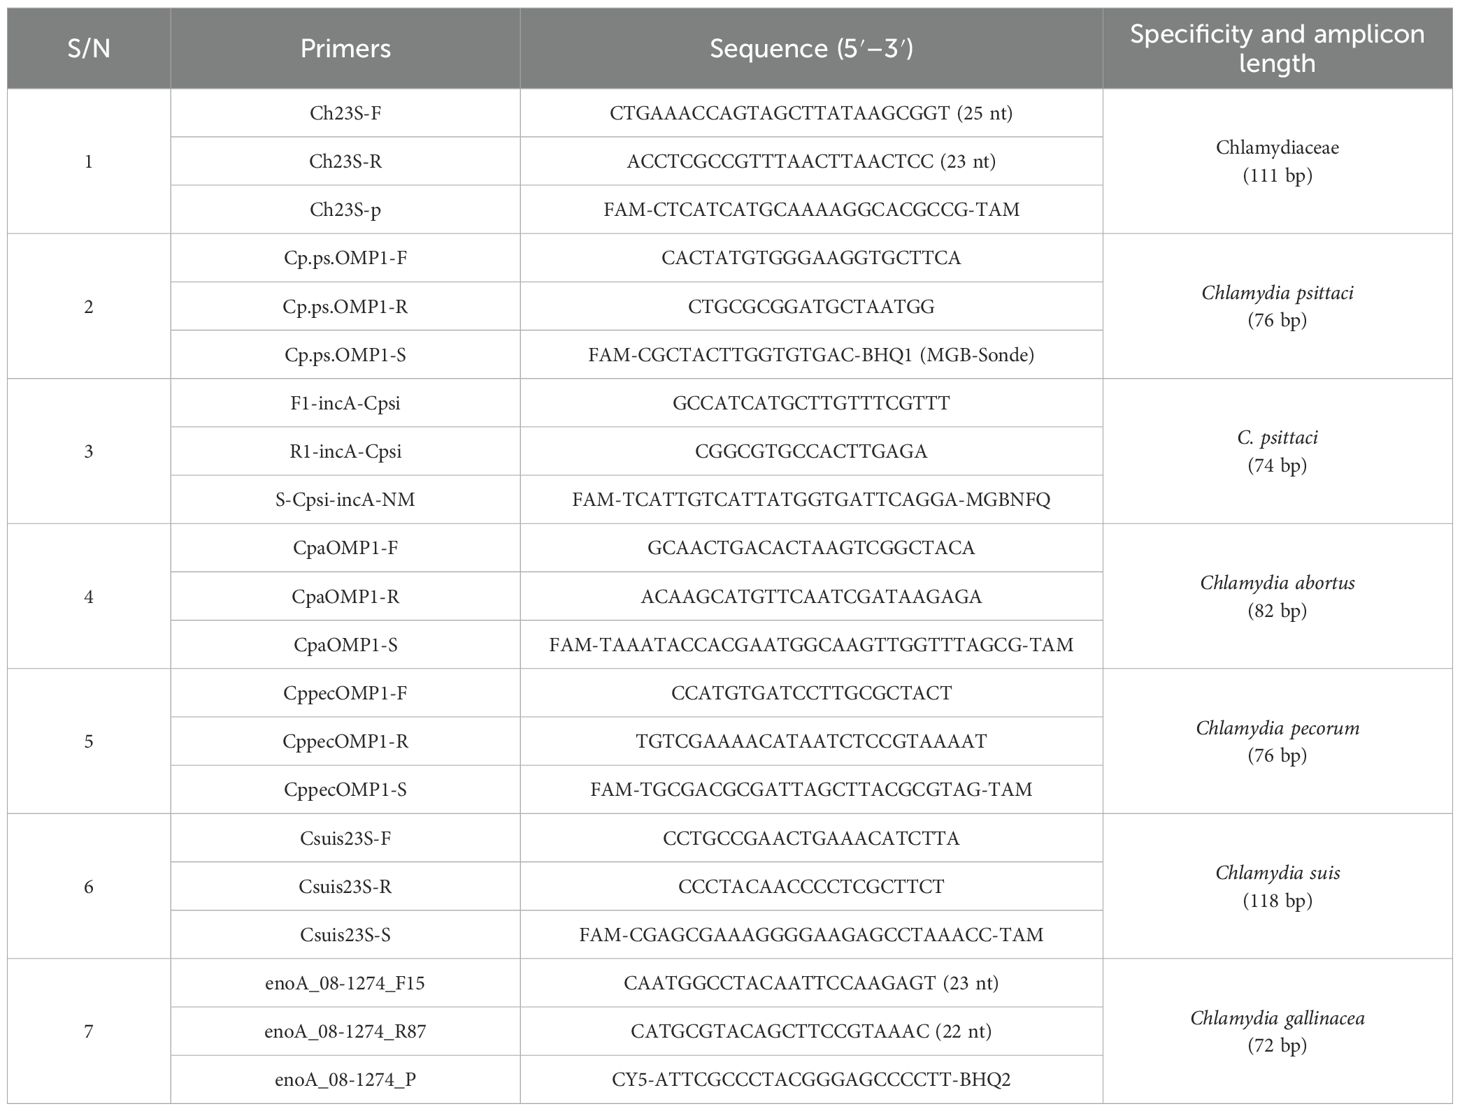

After the patient’s hospital admission, his chest X-ray revealed bilateral pneumonia and ground-glass opacity, and he was prescribed oxygen therapy and doxycycline. Afterward, lesions with ground-glass opacity were reduced, but pulmonary consolidation was still observed in the lungs (Supplementary Figure S2). Based on 23S rDNA amplification, a positive 172-bp band of C. psittaci was detected in the patient’s alveolar wash, while his tracheal mucosa and throat swabs were negative (Figure 1A). Other family members, the nurses, the attending physician, and the house chickens were negative for C. psittaci (Figure 1B). Afterward, qPCR results showed that the patient’s alveolar wash was positive for C. psittaci. Subsequently, positive C. psittaci was identified in the patient’s alveolar wash and throat swab, and his sons’ throat swab. However, a negative reaction was found in his tracheal mucosa and other close contacts’ samples (Figure 2). The ompA gene sequence of the C. psittaci strain was determined and submitted to GenBank (accession number: OR616243). After inoculation into SPF embryonated eggs, typical intracellular inclusions were observed using immunofluorescence staining (Figure 3).

Figure 1. Detection of Chlamydia psittaci from patient’s samples and his close contacts using 23S rDNA PCR. (A) Positive C. psittaci was detected in the patient’s alveolar lavage (M, marker; 1, alveolar lavage; 2, throat swabs; 3, tracheal mucosa; 4, C. psittaci 6BC control; 5, negative control). (B) Negative samples of patient’s close contacts (M, marker; 1–7, patient’s relatives; 8, doctor; 9, nurse; C1–C10, chicken samples; N, negative control; P, positive control).